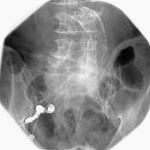

主に、鼠径部(足の付け根付近)の動脈(静脈)、肘/手首の動脈(静脈)からカテーテルと呼ばれる細長い管をX線透視下で目的部位まで誘導し、造影剤を用いて撮影を行うことで、血管などを描出し診断または治療に役立てる検査です。また、IVR(Interventional radiography;放射線介入治療)に移行、または、それを目的として行う割合が増加しています。

当施設では、DSA(Digital Subtraction Angiography;撮影時の造影剤の有無とディジタル処理によって、血管などを明瞭に描出する手法)を有する装置を活用し臨床に役立てています。心血管造影検査(治療)、頭(頚)部造影検査(治療)、肝動脈化学塞栓療法、下肢血管形成術などが一般的ですが、腹部大動脈瘤に対する大動脈ステントグラフト置換術も多く行われてきています。

- 腹腔動脈(DSA)画像